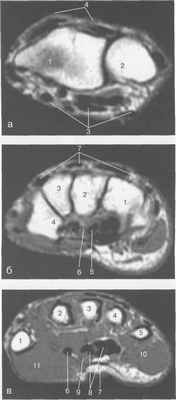

Рис. 19.54. МРТ лучезапястного сустава и кисти в аксиальной плоскости.

а — уровень лучезапястного сустава: 1 — лучевая кость; 2 — локтевая кость; 3 — группа ладонной поверхности сухожилий; 4 — группа тыльной поверхности сухожилий.

б — уровень костей запястья: 1 — крючковидная кость; 2 — головчатая кость; 3 — трапециевидная кость; 4 — кость-трапеция; 5 — группа сухожилий сгибателей; 6 — п. medianus; 7 — группа сухожилий разгибателей.

в — уровень пястных костей: 1 — I пястная кость; 2 — II пястная кость; 3 — III пястная кость; 4 — IV пястная кость; 5 — V пястная кость; 6 — сухожилие m. flexor pollicis longus; 7 — ладонный апоневроз; 8 — сухожилия сгибателей; 9 — п. medianus; 10 — m. abductor digiti munimi; 11 — m. abductor pollicis brevis.